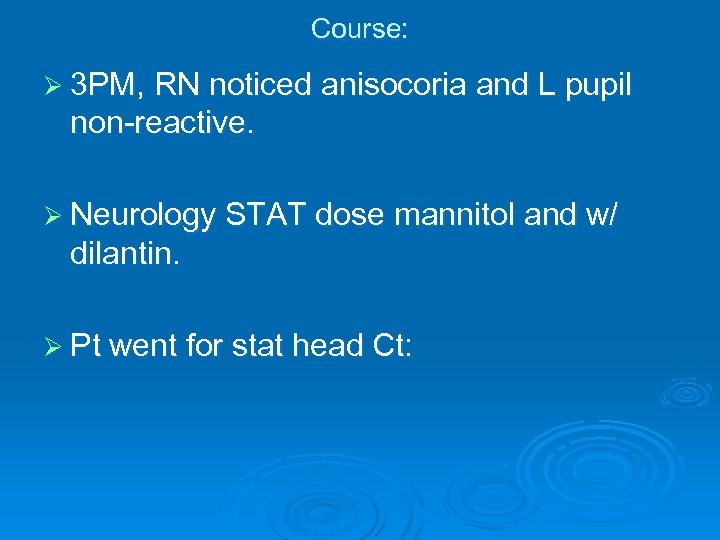

Course: Ø 3 PM, RN noticed anisocoria and L pupil non-reactive. Ø Neurology STAT dose mannitol and w/ dilantin. Ø Pt went for stat head Ct: